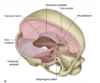

Diagram of the meninges around the brain

Dural infoldings diagram

These dural infoldings partition the brain, and divide the cranial cavity into several compartments.

How many dural infoldings are there? What are they called?

3 folds:

- Falx cerebri

- Tentorium cerebelli

- Falx cerebelli

Where is the falx cerebri located?

Between the two cerebral hemispheres (forms a sickle shape from front to back)

Where is the tentorium cerebelli located?

Separates the cerebral hemispheres from the cerebellum below (tent over the cerebellum) –> divides the cranial cavity into supratentorial and infratentorial compartments

Where is the falx cerebelli located?

It is a small infolding of the dura in the sagittal plane over the floor of the posterior cranial fossa. Separates the two cerebellar hemispheres

What are the attachments of the falx cerebri?

Anterior: crista galli of ethmoid bone

Posterior: inner surface of occipital bone (internal occipital protuberance)